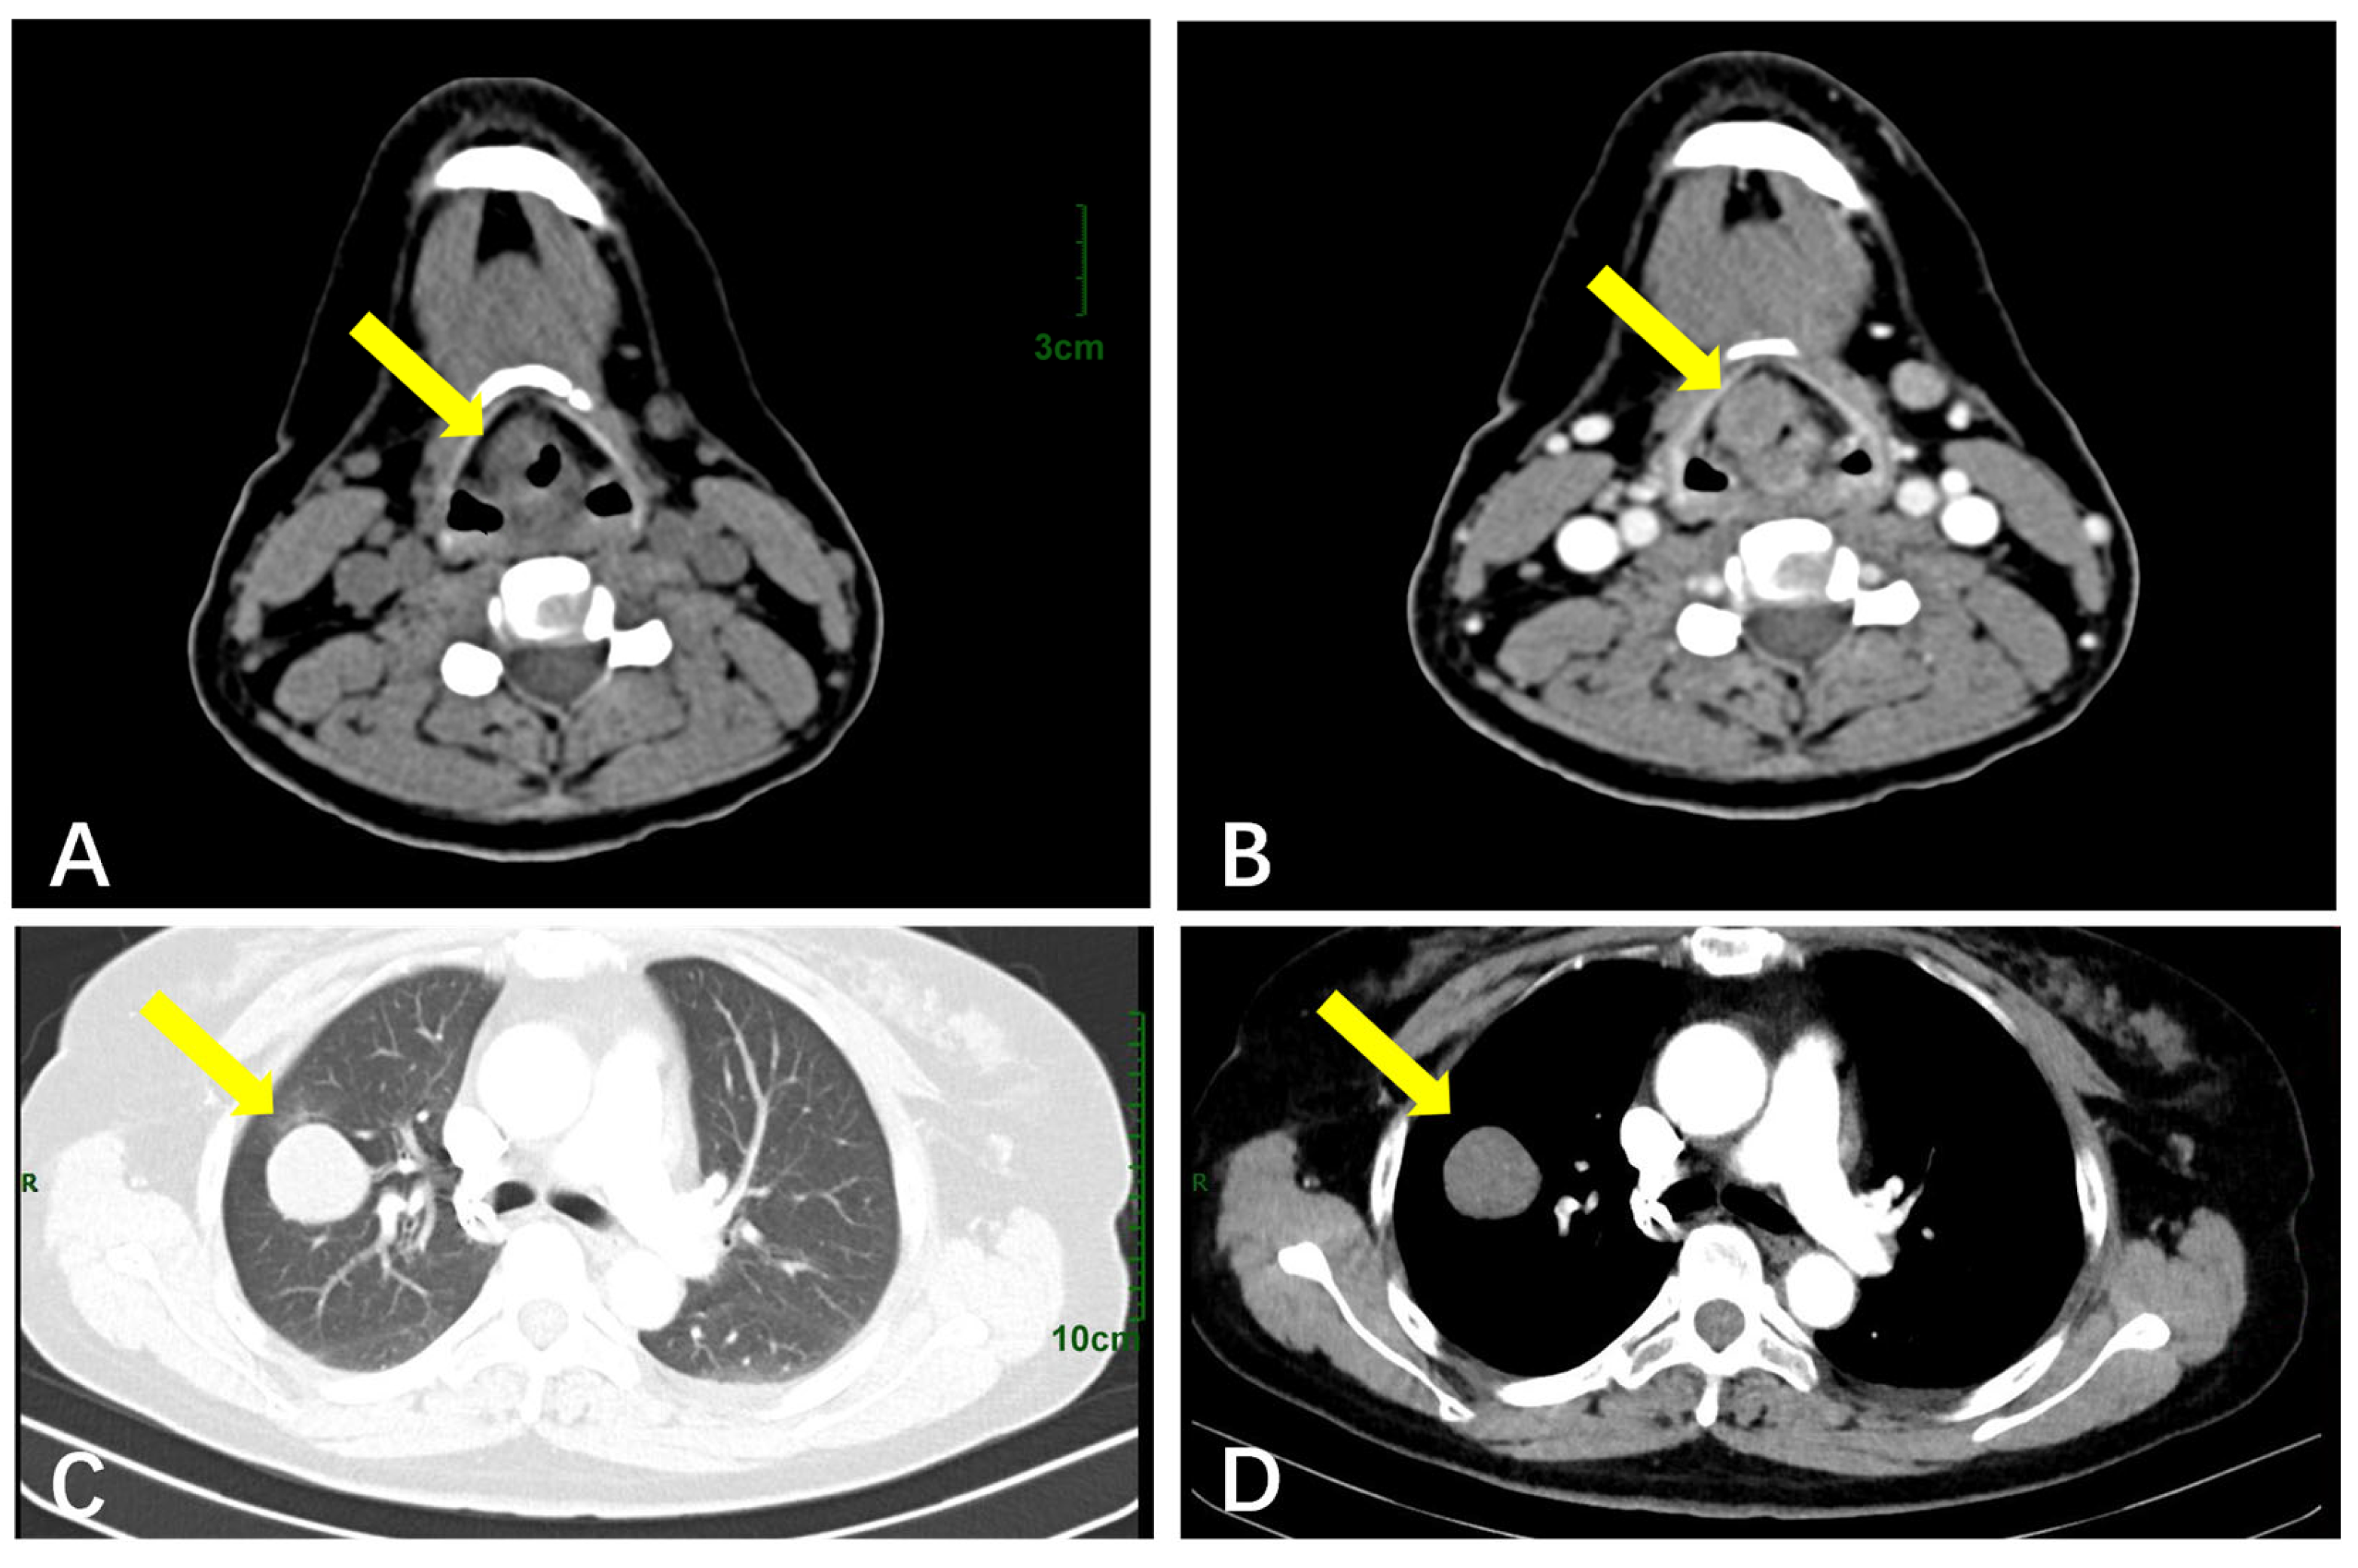

3.2.3. The Respiratory System

| Respiratory System | CT (n = 5) | Round/oval hypodense masses; lobulated contours; mild–moderate enhancement | A larger size (mean: 50 mm); no pathognomonic signs. |